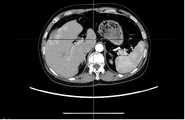

Fig. 8a is a schematic diagram of a sequence of CT images viewed from a transverse direction.

fig. 8a-8c are raw three-dimensional data of sequential CT images viewed from three directions, the transverse, sagittal and coronal planes, respectively. Fig. 9a to 9c are the second binarized images obtained after the method removes the bed plate area, respectively, and it can be seen from fig. 9a to 9c that none of the skin surface contours of the human body area is damaged. Fig. 10a to 10c are respectively third binarized images obtained after filling the cavity by the method, and it can be seen from fig. 10a to 10c that the third binarized images are completely overlapped with the original three-dimensional data of the sequence CT image, and the lung region with a low threshold value is effectively filled. As can be seen from FIGS. 11a-11d, after another serial CT image is reconstructed by the method, the three-dimensional model of the skin can be fused with the third binary image and the serial CT image. And finally mapping the obtained three-dimensional model of the skin back to a 2D mode, and comparing the coincidence degree of the skin boundary in the three-dimensional model of the skin and the binary image to obtain figures 12a-12 c. In addition, the three-dimensional models of the skin of other parts of the human body obtained by the method are shown in figures 13a-13 c.